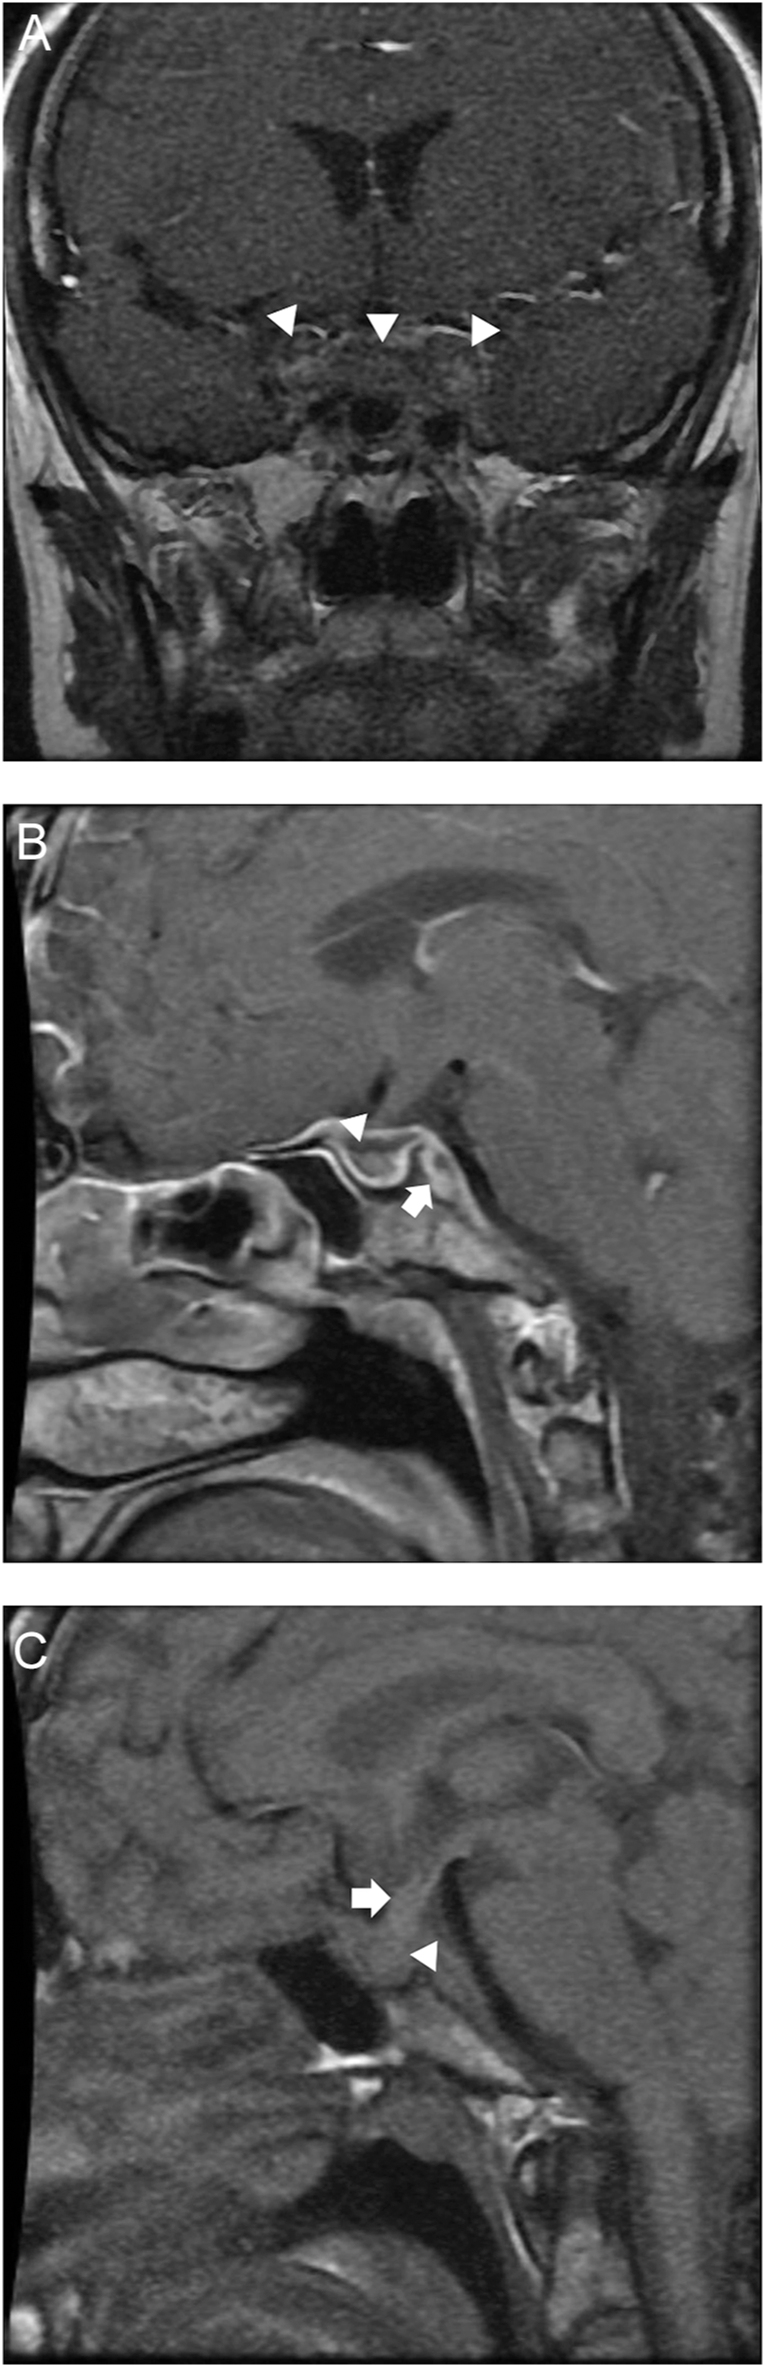

Summary: A 39-year-old woman presented with a 5-year history of severe intermittent headaches, rhinitis, hemoptysis, unintentional weight loss of 40 kg over a year, and unilateral vision loss. Then, she noticed polyuria, amenorrhea, muscle weakness, and cold intolerance. Diagnosis of granulomatosis with polyangiitis (GPA) was confirmed with elevated c-ANCA levels and PR3-positive antibodies. Physical examination revealed hypotension, absence of pubic and axillary hair, and classical signs of hypothyroidism. The patient reported multiple previous hospitalizations due to episodes of hypernatremia, hypotension, and hypoglycemia. The biochemical evaluation showed early signs of chronic kidney disease and central adrenal, thyroid, and gonadotropin deficiencies. Pituitary MRI revealed a heterogeneous pituitary gland with peripheral enhancement, central necrosis, and extension to adjacent structures, as well as the absence of posterior pituitary bright spot on T1-weighted imaging. A diagnosis of GPA with pituitary involvement was established. Remission therapy with corticosteroids and rituximab was started. After disease control, pituitary hormonal deficiencies persisted, requiring long-term hormone replacement therapy.